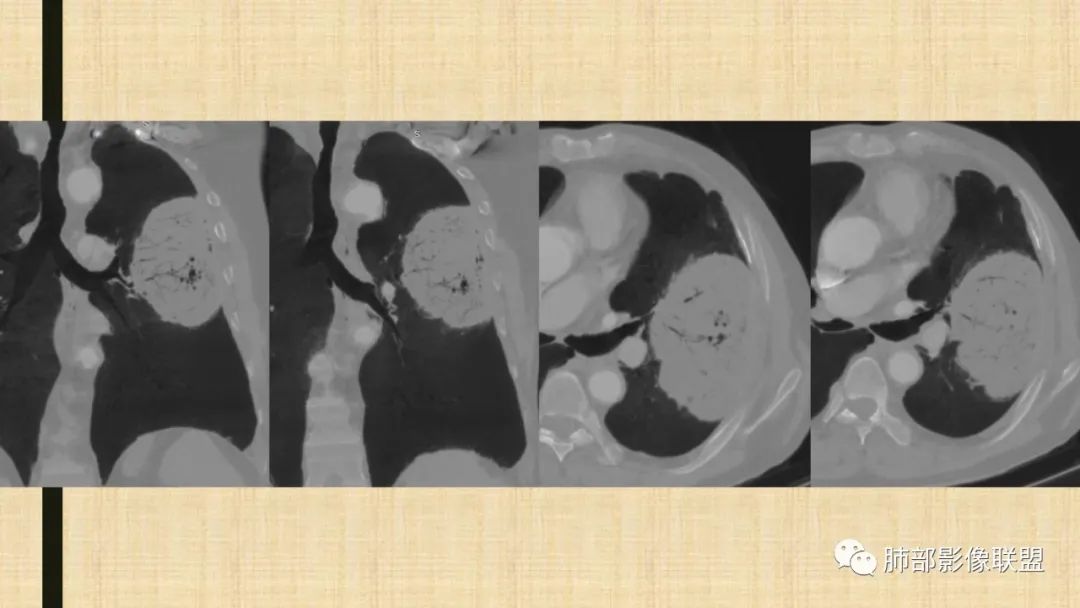

左肺上叶大肿块,膨胀性生长,边界清,密度较低,见部分坏死区,强化弱,肿块见支气管充气V扩张征,分布僵直,枯树枝特点,另一个重要特点血管造影征,淋巴瘤,肿块长轴与胸膜平行,与隐球菌鉴别,隐球荚膜抗原检查,明确诊断经皮肺穿刺。另胸膜钙化(问诊既往有无患胸膜炎病史)。

左肺上叶胸膜下肿块,宽基底与胸膜相连,跨叶裂,边缘清晰膨隆,其内支气管充气,部分扩张、僵直,无明显强化,血管造影征,考虑淋巴瘤,鉴别腺癌

左肺胸膜下巨大占位,跨叶裂,宽基底与胸膜相连,胸膜钙化,平扫密度较低,强化不明显,可见内部血管显影,支气管充气征和扩张,考虑为恶性,倾向于淋巴瘤

左肺上叶胸膜下肿块,膨胀性生长,边界清晰,密度不均部分坏死,未见强化,病灶内支气管迂曲扩张,病灶长轴与胸膜平行,胸膜下脂肪间隙存在,胸膜钙化,考虑放线菌?毛霉?鉴别淋巴瘤

左肺上叶肿块,宽基底与胸膜相连,跨叶裂,边缘清晰膨隆,可见小分叶,其内支气管充气,部分扩张、僵直,呈枯枝征,支气管达边征,增强无明显强化,可见血管造影征,考虑恶性病变,淋巴瘤,鉴别粘液腺癌。

大肿块,边缘光滑,深分叶

近端支气管堵塞、推移为主

部分类似于脐凹征

内部支气管扩张

肺动脉推移为主,边缘部分进入

大肿块、表面光滑但深分叶,肺门侧支气管堵塞

回头看,内部支气管近端其实不连续,伴随肺动脉不存在

1)部位:周围型或中央型软组织肿块,以周围型为多见,且肿瘤多位于肺上叶。如本例:该肿瘤位于左肺上叶。

2)大小及形态:由于本病恶性程度高,早期症状不明显,发现时肿块均较大。如本例病变巨大。

3)肿块边界和边缘:多较清楚,呈圆形、类圆形,且由于肿块生长速度不均匀,可见分叶,毛刺少见。有报道肿块周围毛玻璃影是多形性癌特征表现。

4)密度:肿块平扫为软组织密度,由于体积较大,内部常见大片状坏死,可出现不规则厚壁空洞或坏死内多发无壁小空洞,坏死多不均匀:坏死灶内可见如柳絮样的斑片样强化灶,坏死边缘与非坏死区分界不清本例坏死较明显,密度不均匀。

5)肿瘤强化方式:肺部恶性肿瘤强化程度与其血供丰富程度相关,血供丰富多强化明显,反之则较差。由于PSC 周边实性部分富血供及内部黏液变性、坏死,增强后肿块多数呈轻-中度边缘环形强化或不均匀小斑片状强化。国外学者对照病理发现肿瘤细胞或胶原组织增强扫描时强化,无强化的低密度区代表了黏液样变性区和出血坏死区。